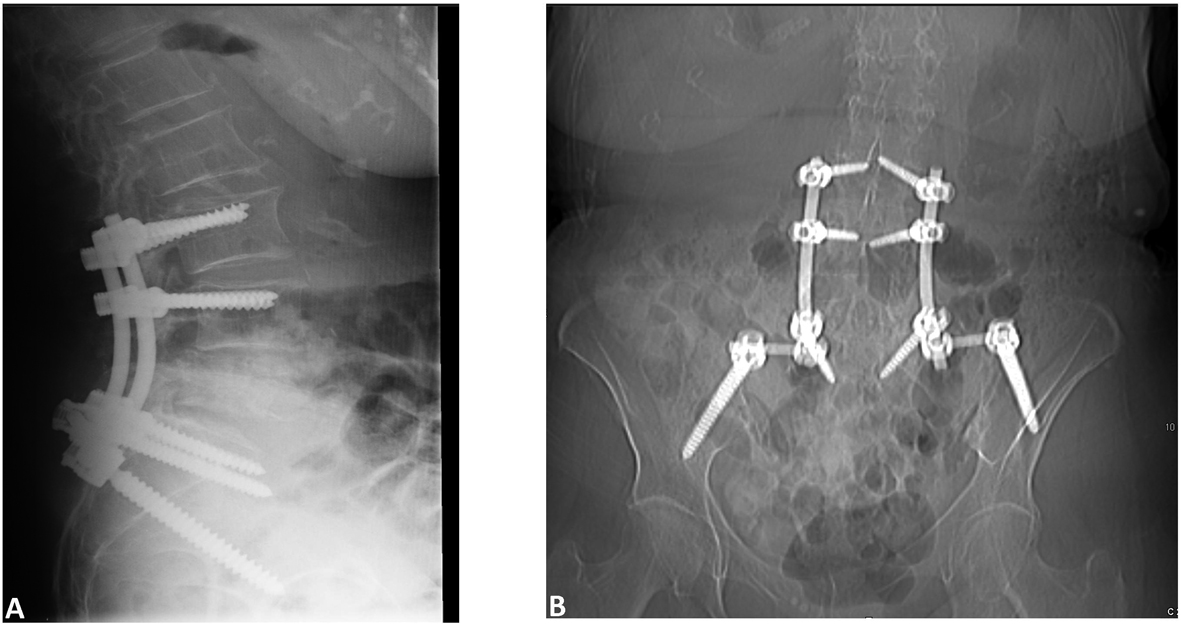

She underwent L4-L5 laminectomy and right transpedicular approach for decompression of the burst fracture. Upon exposure of the burst fracture a soft tissue mass was palpated ventral to the thecal sac. The canal was decompressed and the sac was released of any pressure. L3 to iliac posterior spinal fusion with instrumentation was carried out with placement of bilateral pedicle screws (Fig. 2A, B). Graft arthrodesis was done using 10 mL Grafton DBM Crunch (Osteotech Inc., Eatontown, New Jersey) and 30 mL cancellous bone. Due to the oncologic nature of the procedure neither local bone nor BMP was utilized. The patient was monitored during the procedure with somatosensory evoked potentials (SSEP) without any significant changes.

![]() Click for large image | Figure 2. Postoperative (A) Sagittal and (B) AP images showing placement of screws. |